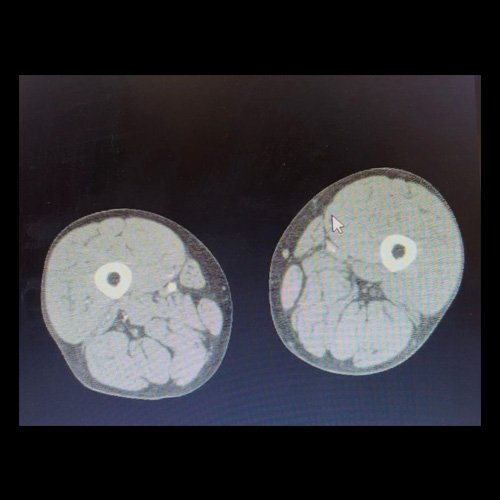

• AngioTAC de miembros inferiores (Día 2): Ateromatosis parietal calcificada parcheada en todo el territorio aorto-ilíaco-femoral bilateral. LADO DERECHO: Arteria ilíaca interna: de calibre y trayecto conservado, permeable. Arterias ilíaca externa y femoral común: de calibre y trayecto conservados, permeables. Arterias circunfleja ilíaca superficial y epigástrica superficial: de calibre y trayecto conservados, permeables. Arteria femoral superficial: de calibre y trayecto conservado, permeable. Arteria femoral profunda: de calibre y trayecto conservado, permeable. Arterias circunflejas femoral medial y lateral: de calibre y trayecto conservados, permeables. Arteria poplítea: de calibre y trayecto conservado, permeable. Arteria tibial anterior: de calibre y trayecto conservado, permeable. Arteria tibial posterior: de calibre y trayecto conservado, permeable. Vena ilíaca primitiva: 13 mm, vena ilíaca externa 11 mm, vena ilíaca interna 7 mm. LADO IZQUIERDO: En esta ocasión, en fase angiográfica se observa de calibre y opacificación conservada de las arterias femoral superficial y profunda, poplítea y de sus ramas musculares en muslo y pierna. En fase venosa se evidencia un defecto de relleno endoluminal de la vena primitiva izquierda que impresiona extenderse actualmente a la vena iliaca externa, a la vena femoral superficial y poplítea, hasta nivel del hueco homonimo, las cuales se visualizan aumentadas de calibre con respecto a sus contralaterales, en relación a trombosis venosa profunda. Se sugiere cotejar con ecodoppler de miembros inferiores. No se identifica compromiso de la porción visualizada de la vena cava inferior ni del sistema venoso ilíaco contralateral. Se visualiza dispositivo vascular en VCI (filtro VCI), infrayacente a las venas renales. Presenta aumento del diámetro del muslo izquierdo con respecto a su contralateral, asociado a edema de los tejidos blandos superficiales. Reticulación de la grasa de la región inguinal a predominio izquierdo con algunas burbujas aéreas. Se observa inmediatamente infrayacente a los antes mencionado, un área hiperdensa que realza en fase venosa, con centro hipodenso, que mide 2.2 cm x 1.4 cm, ya visualizado en tomografía previa. Cambios artrodegenerativos coxo-femorales y tricompartimentales en la rodilla. Signos de entesopatía cuadricipital distal. No se observan alteraciones a nivel del fémur ni de las porciones visualizadas de la tibia y el peroné. Arteria ilíaca interna: de calibre y trayecto conservado, permeable. Arterias ilíaca externa y femoral común: de calibre y trayecto conservados, permeables. Arterias circunfleja ilíaca superficial y epigástrica superficial: de calibre y trayecto conservados, permeables. Arteria femoral superficial: de calibre y trayecto conservado, permeable. Arteria femoral profunda: de calibre y trayecto conservado, permeable. Arterias circunflejas femoral medial y lateral: de calibre y trayecto conservados, permeables. Arteria poplítea, tibial anterior y tibial posterior: de calibre disminuido con respecto a su contralateral, permeables. Vena ilíaca primitiva: 14 mm, vena ilíaca externa 17 mm, vena ilíaca interna 9 mm. Calcificaciones en conducto inguinal bilateral. Hidrocele bilateral.

Angio TAC de miembros inferiores (Día 2)